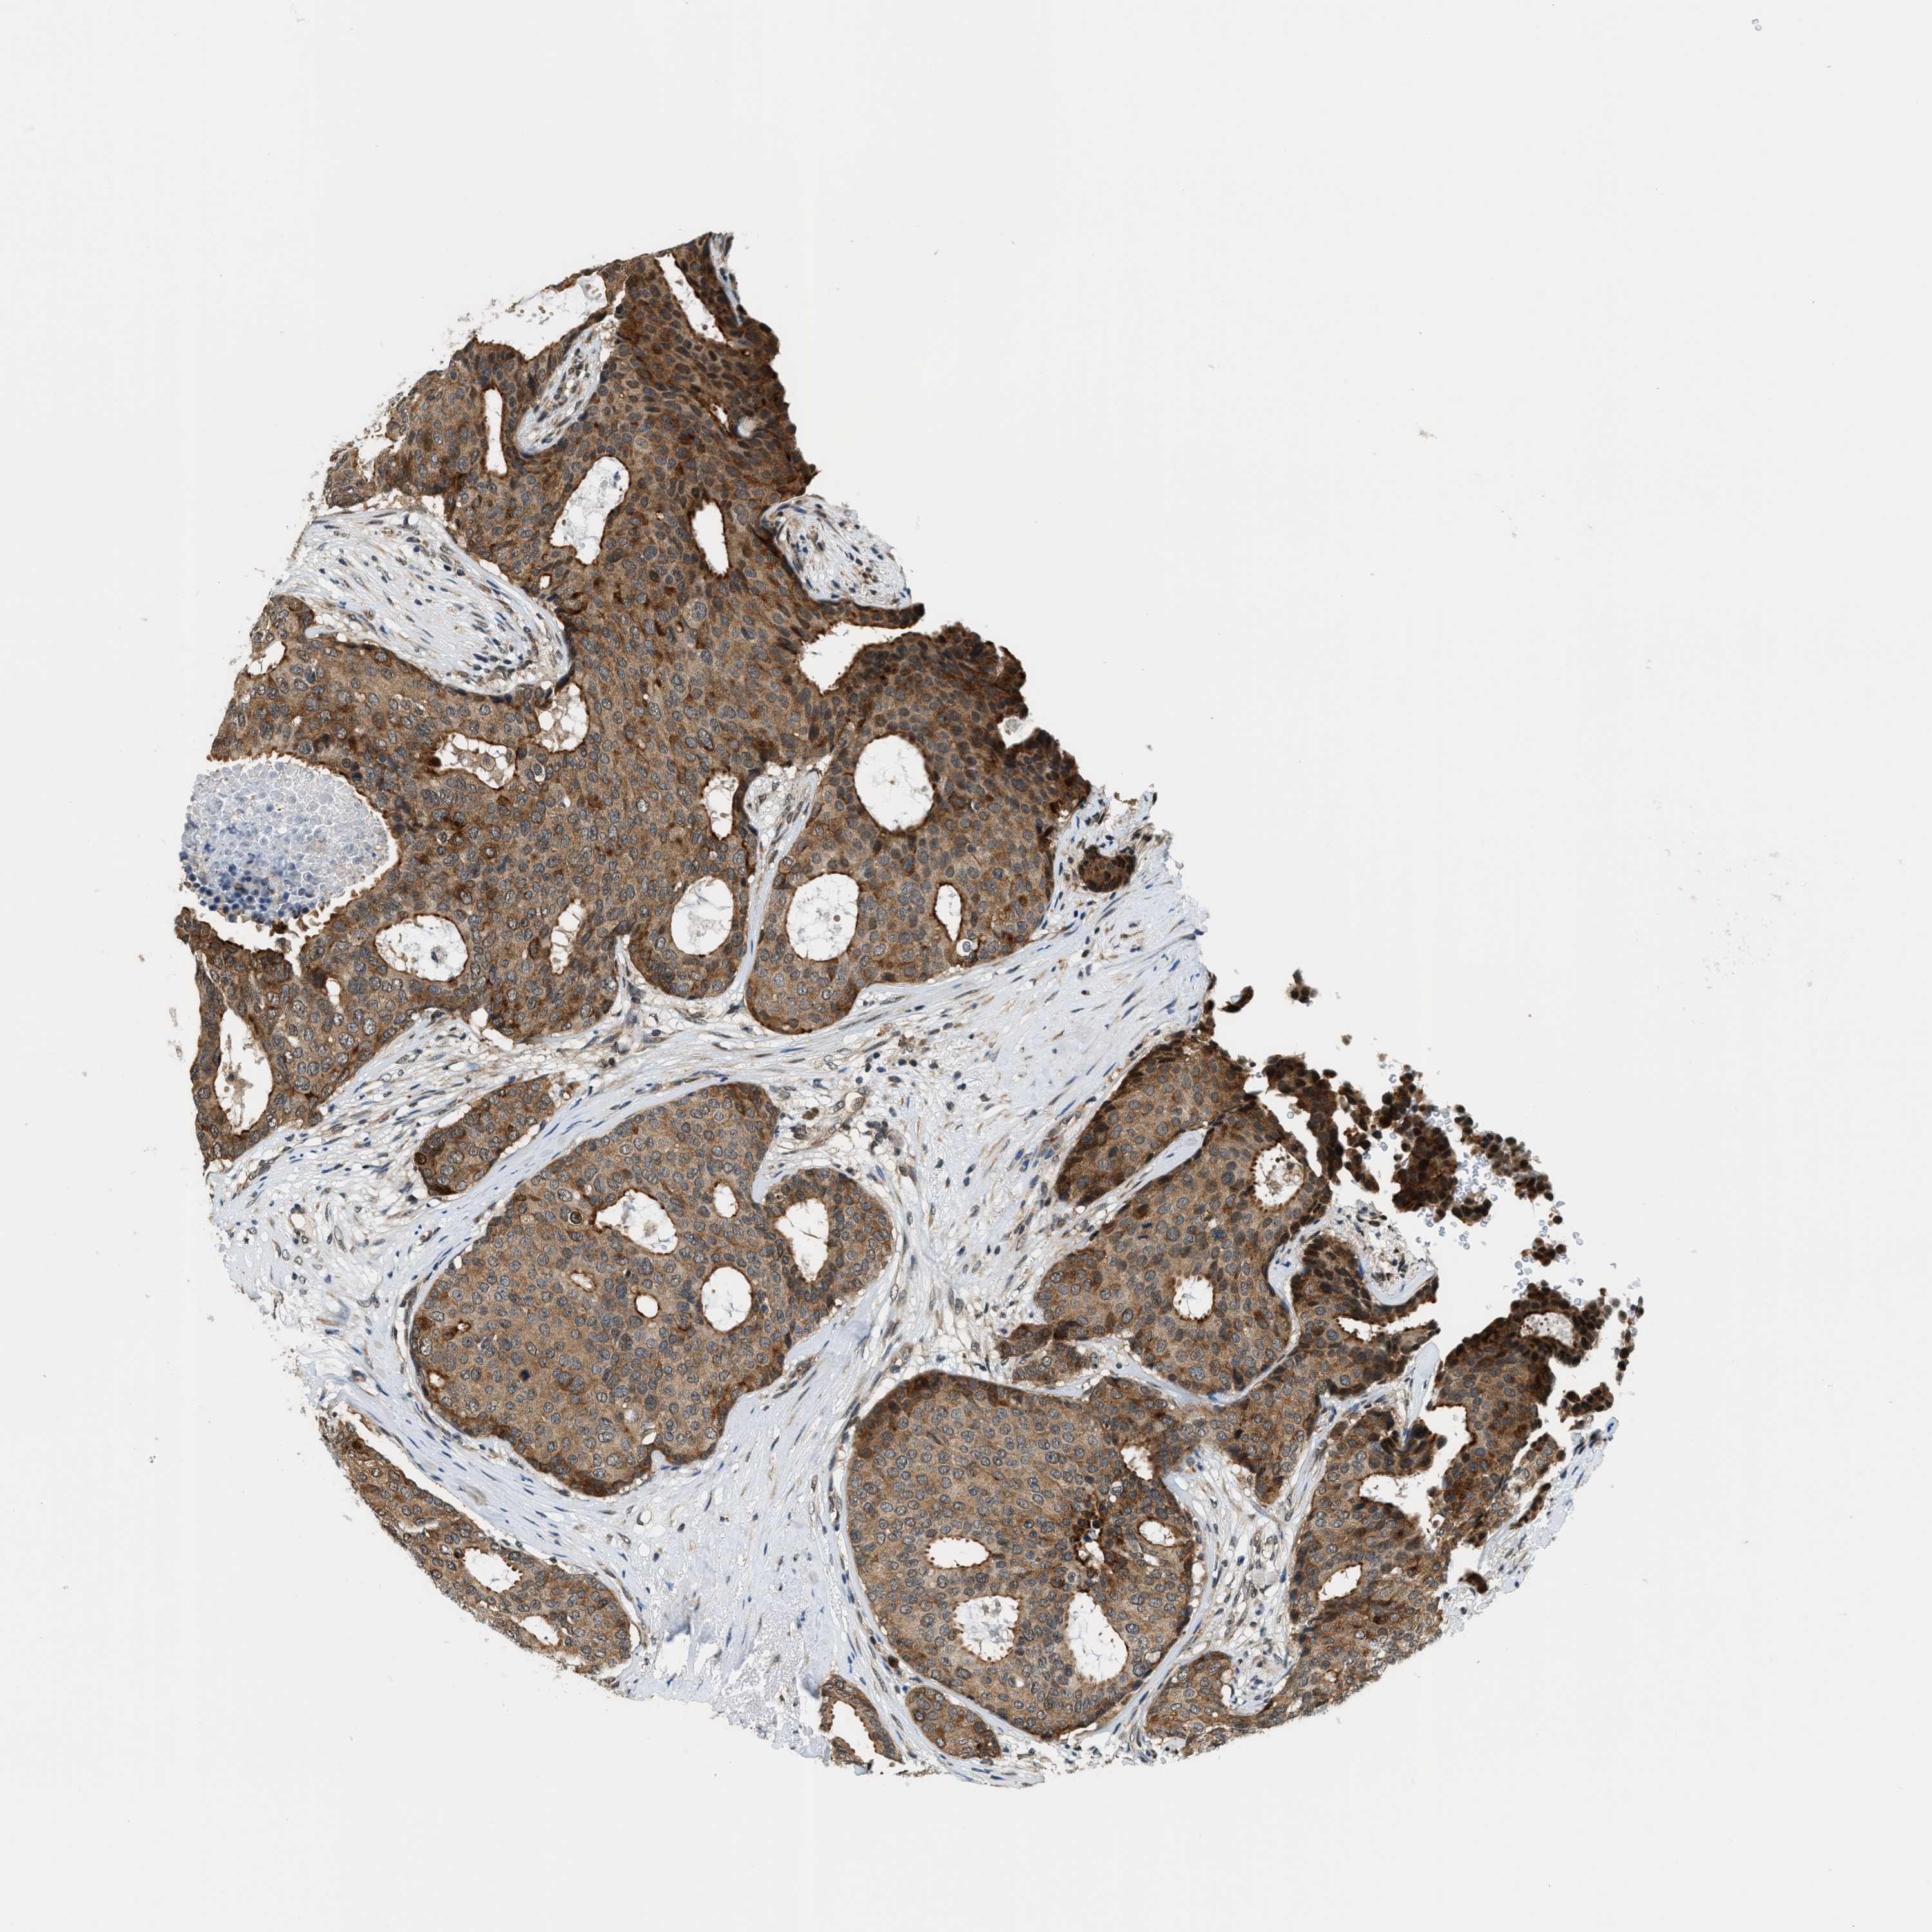

BRCA TCGA BRCA VALIDATION PROTEIN EXPRESSION